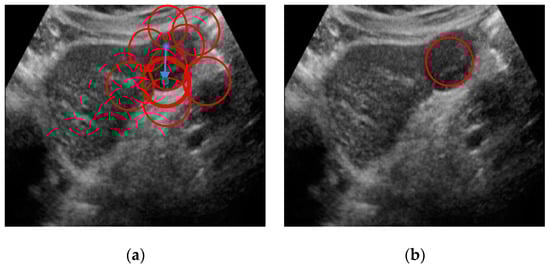

2.6. Lesion Region Finding

The output segment in this study is proposed to mark the possible lesion region if the image is detected as liver lesion. The liver lesions are of different shape and size varying with the lesion types. Whenever any region is detected as lesion, a circle is marked around that region. The patches are connected after classification to detect the center coordinate. The coordinates of overlapping circles are used to find the possible lesion region. A center is selected as the final center where most of the circles are overlapped. The distance between the final center and the minimum overlapped center is maximized to obtain final radius. Algorithm 1 demonstrates the procedures of detecting lesion regions. The marking instance of liver lesion is shown in Figure 6 according to our working algorithm.

Figure 6. Output image with marked lesion: (a) all marked patches with center and radius (b) Final lesion region.